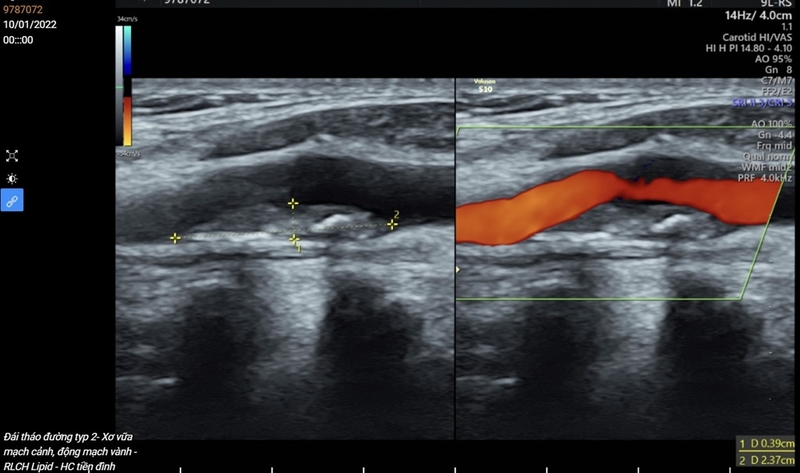

Kỹ thuật siêu âm tĩnh mạch chi dưới không quá phức tạp và được tiến hành trong thời gian ngắn. Theo cấu tạo cơ thể, mạch chi dưới được chia thành 2 loại là động mạch và tĩnh mạch. Bác sĩ sẽ dùng kỹ thuật siêu âm B - mode, siêu âm doppler màu, siêu âm doppler xung. Tần số của sóng siêu âm được sử dụng là 5 MHz. Người bệnh được đặt ở tư thế ngồi, nằm hoặc đứng tùy theo yêu cầu của bác sĩ thăm khám.

Quá trình khảo sát và siêu âm sẽ tiến hành từ tầng đùi, bao gồm động mạch đùi chung, đùi nông, đùi sâu đoạn gần và đoạn xa đến tầng đùi gồm động mạch khoeo, kế tiếp là tầng cẳng chân gồm động mạch mác, động mạch chày trước, động mạch chày sau. Khi bắt đầu siêu âm, bác sĩ quét đầu dò đến các vị trí động mạch cần siêu âm, sau đó quan sát kỹ hình ảnh được hiển thị trên màn hình, từ đó phát hiện các tổn thương hoặc bệnh lý ở khu vực chi dưới.